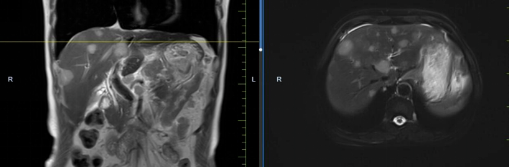

患者馬某某,男,60歲,因腹部不適行胃鏡及腹部CT,提示胃癌、多發(fā)淋巴結(jié)轉(zhuǎn)移、肝轉(zhuǎn)移,胃部病灶大小約11*6cm,淋巴結(jié)最大病灶約6*3cm,肝臟病灶最大約8.8*7cm。經(jīng)6周期化療+免疫,聯(lián)合中醫(yī)中藥后,病灶明顯縮小,進(jìn)入維持治療階段,身體狀況與常人無(wú)異。

治療后